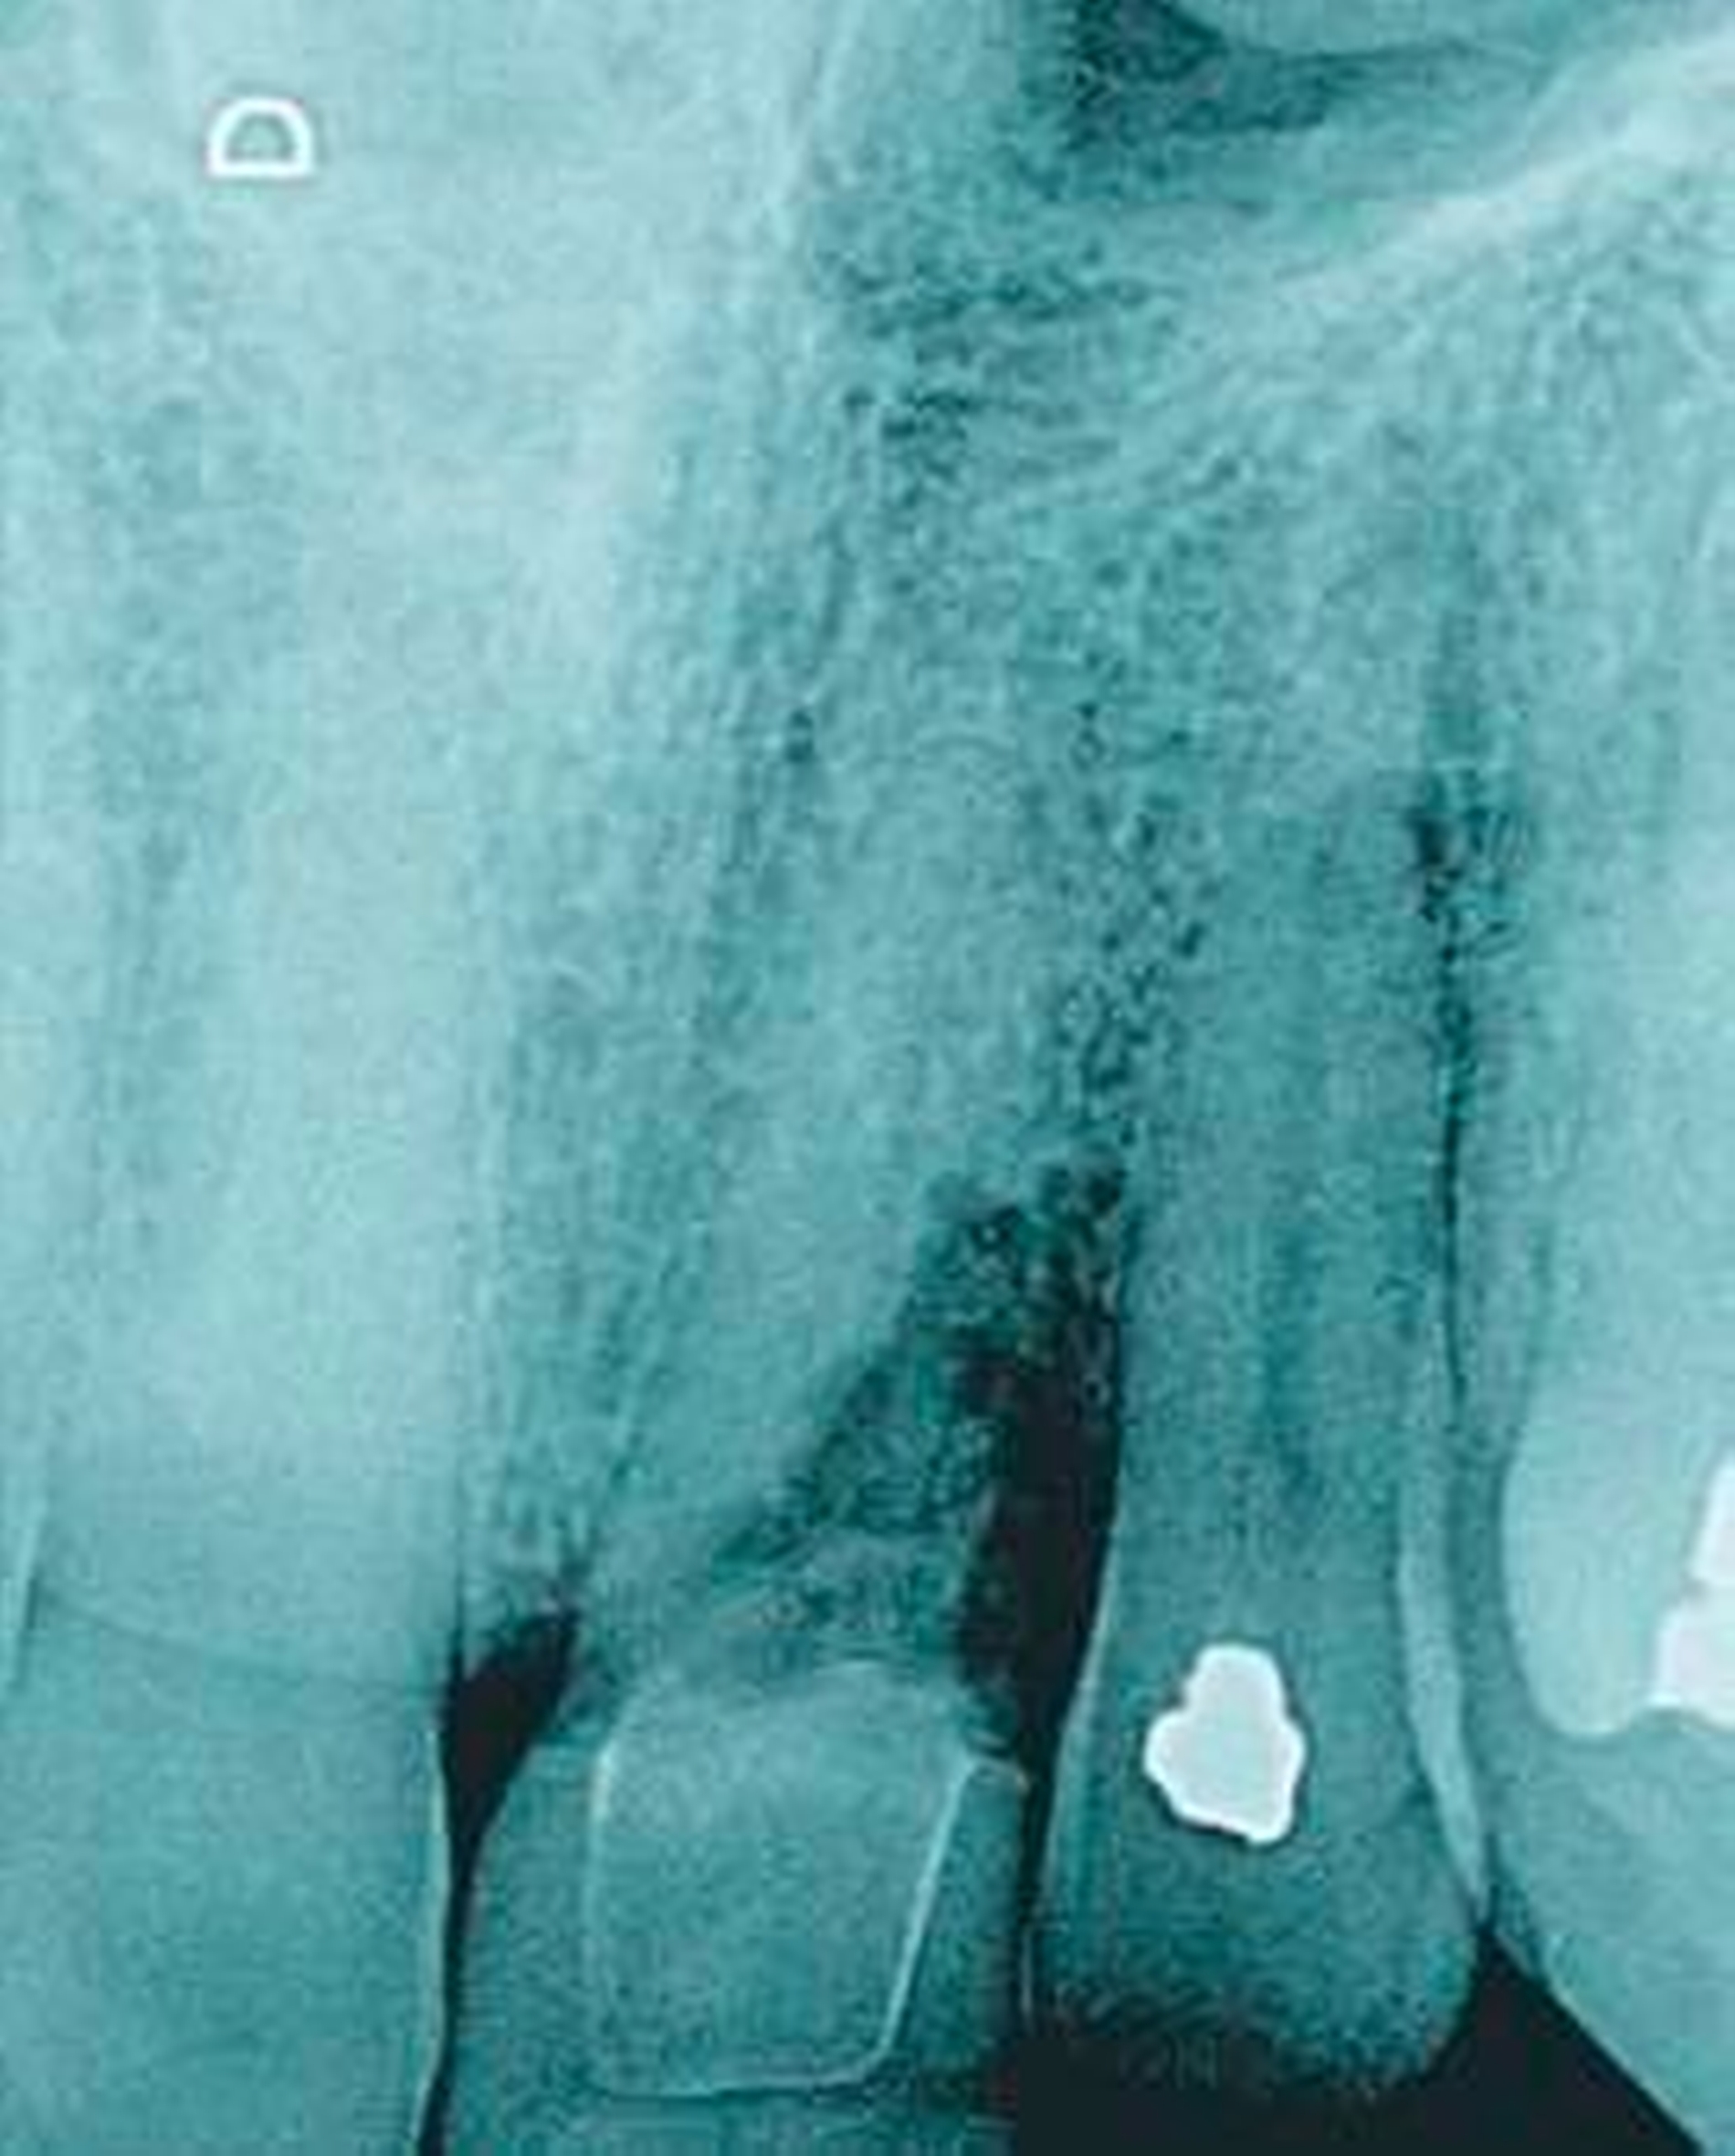

Nicht selten kommt es aber auch zur Perforation sowohl des Pulpakammerbodens als auch im Verlauf der Wurzelkanäle. Dies tritt insbesondere dann auf, wenn nicht genügend Zeit für die Behandlung zur Verfügung stand und eine Wurzelkanalbehandlung anstelle einer

reinen Schmerztherapie „zwischendurch“ eingeleitet wurde (siehe Abbildung 6).

Frakturen

Akute Schmerzen entstehen häufig nach Frakturen (sowohl vertikale, als auch horizontale). Diese sind röntgenologisch nur bei einer Dislokation der Frakturstücke sicher zu diagnostizieren (Abbildung 8: röntgenologische Dislokation der Frakturstücke). Aufgrund dessen ist der endodontische Befund durch einen parodontalen Befund des betreffenden Zahnes zu ergänzen. Sollte hier ein tiefer lokalisierter Knochenabbau festgestellt werden, ist eine vertikale Fraktur in Erwägung zu ziehen. Auch eine Anfärbung (Methylenblau) kann die Diagnose sichern. Zwar treten vertikal Frakturen gehäuft bei den Zähnen auf, die mit einem Metallstift oder einer Schraube postendodontisch versorgt worden sind, jedoch muss auch bei endodontisch behandelten Zähnen ohne diese Versorgung eine mögliche Fraktur für die Schmerzen in Betracht gezogen werden.